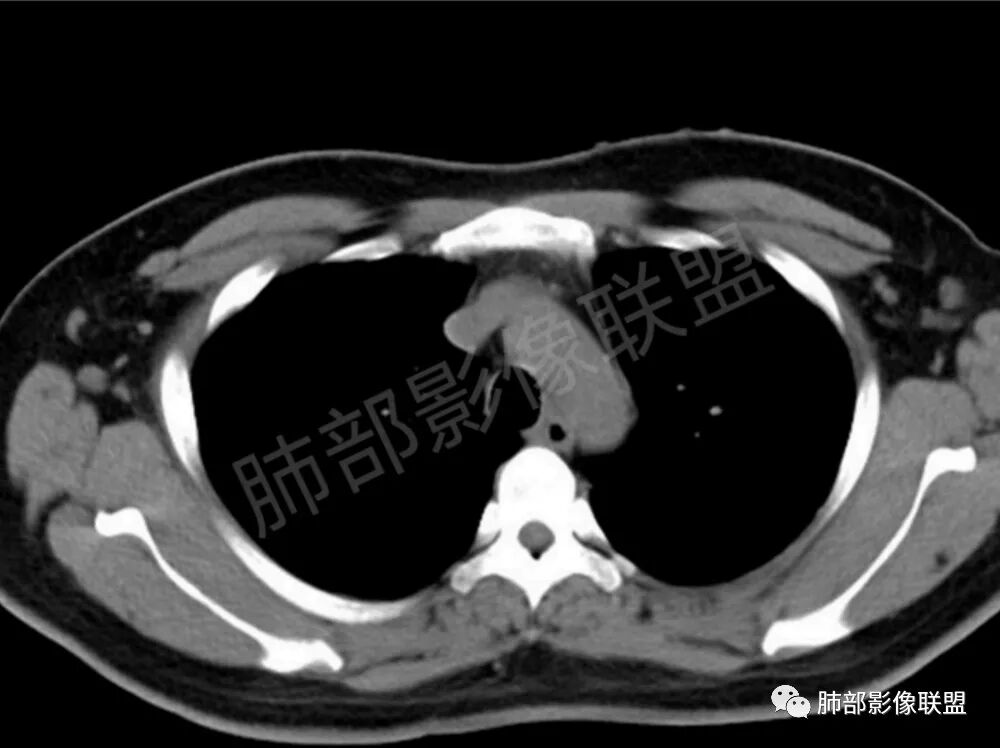

男性,22岁,HIV病史,症状半年,双肺多发大小不等结节影,边缘光滑,密度均匀,以胸膜下分布为主,部分与胸膜相连,胸膜下脂肪间隙可见,病灶近段支气管走行病灶内,远端似有堵塞,无增强图像,考虑隐球菌,鉴别:淋巴瘤,GPA

双肺多发结节影,膨隆,边缘光滑,圆顿,沿支气管血管束分布为主,部分贴胸膜,部分见空洞,空气支气管征

两肺多发结节性,大部分位于胸膜下,部分结节周围可见晕征。局部结节内可见扩张的支气管,纵隔淋巴结大,脾大,22岁男,HIV阳性,常规先考虑隐球菌。鉴别淋巴瘤,结核,马儿。

男,22,半年前咳嗽伴少痰,查HIV阳性,痰查TB阳性,既往有肺部斑片影伴空洞、纵隔淋巴结肿大、脾大。SCC、CA50、CA199、FER增高,此次胸部CT:两肺多发结节影,部分沿血管束分布,部分贴胸膜下,大小不一,密度不一,部分较散、边缘模糊,部分较实、圆钝、周围模糊晕,部分结节有支气管进入穿行自然,部分结节有血管分支自如通过。考虑HI∨相关淋巴增殖类病变,淋巴瘤?LYG?鉴别PC、TB。

青年男性,半年前咳嗽,HIV阳性,结核DNA阳性,肿标糖类抗原和铁蛋白增高。外院影像有纵隔淋巴结增大伴脾大,肺部病灶空洞。现在影像:肺内多发沿支气管分布(有支气管充气征,长轴沿支气管分布)及胸膜下分布(平行于胸膜)的大小不等结节,个别伴有空洞,双侧腋窝淋巴结肿大。纵隔图片不够,是否还有淋巴结肿大未知,脾脏未显示。

1.双肺多发大小不一结节,外围为主,边界尚清,部分周围似有GGO

2.类圆形,部分与胸膜相连,糊墙

3.支气管通畅或近端堵塞